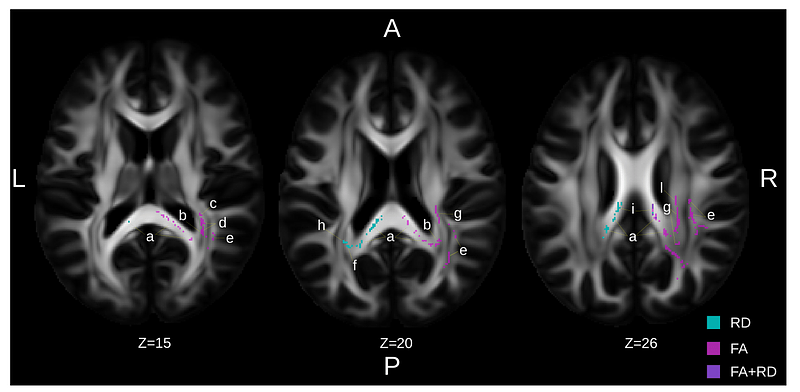

Structural brain improvements following individually tailored serious exergame-based training in mild neurocognitive disorders: exploratory randomized controlled trial

Patrick Manser, Michael Rosio, André Schmidt, Lars Michels, Eling D. de Bruin

Alzheimer's Research & Therapy, vol. 17(1), 2025 Sep 8, p. 190